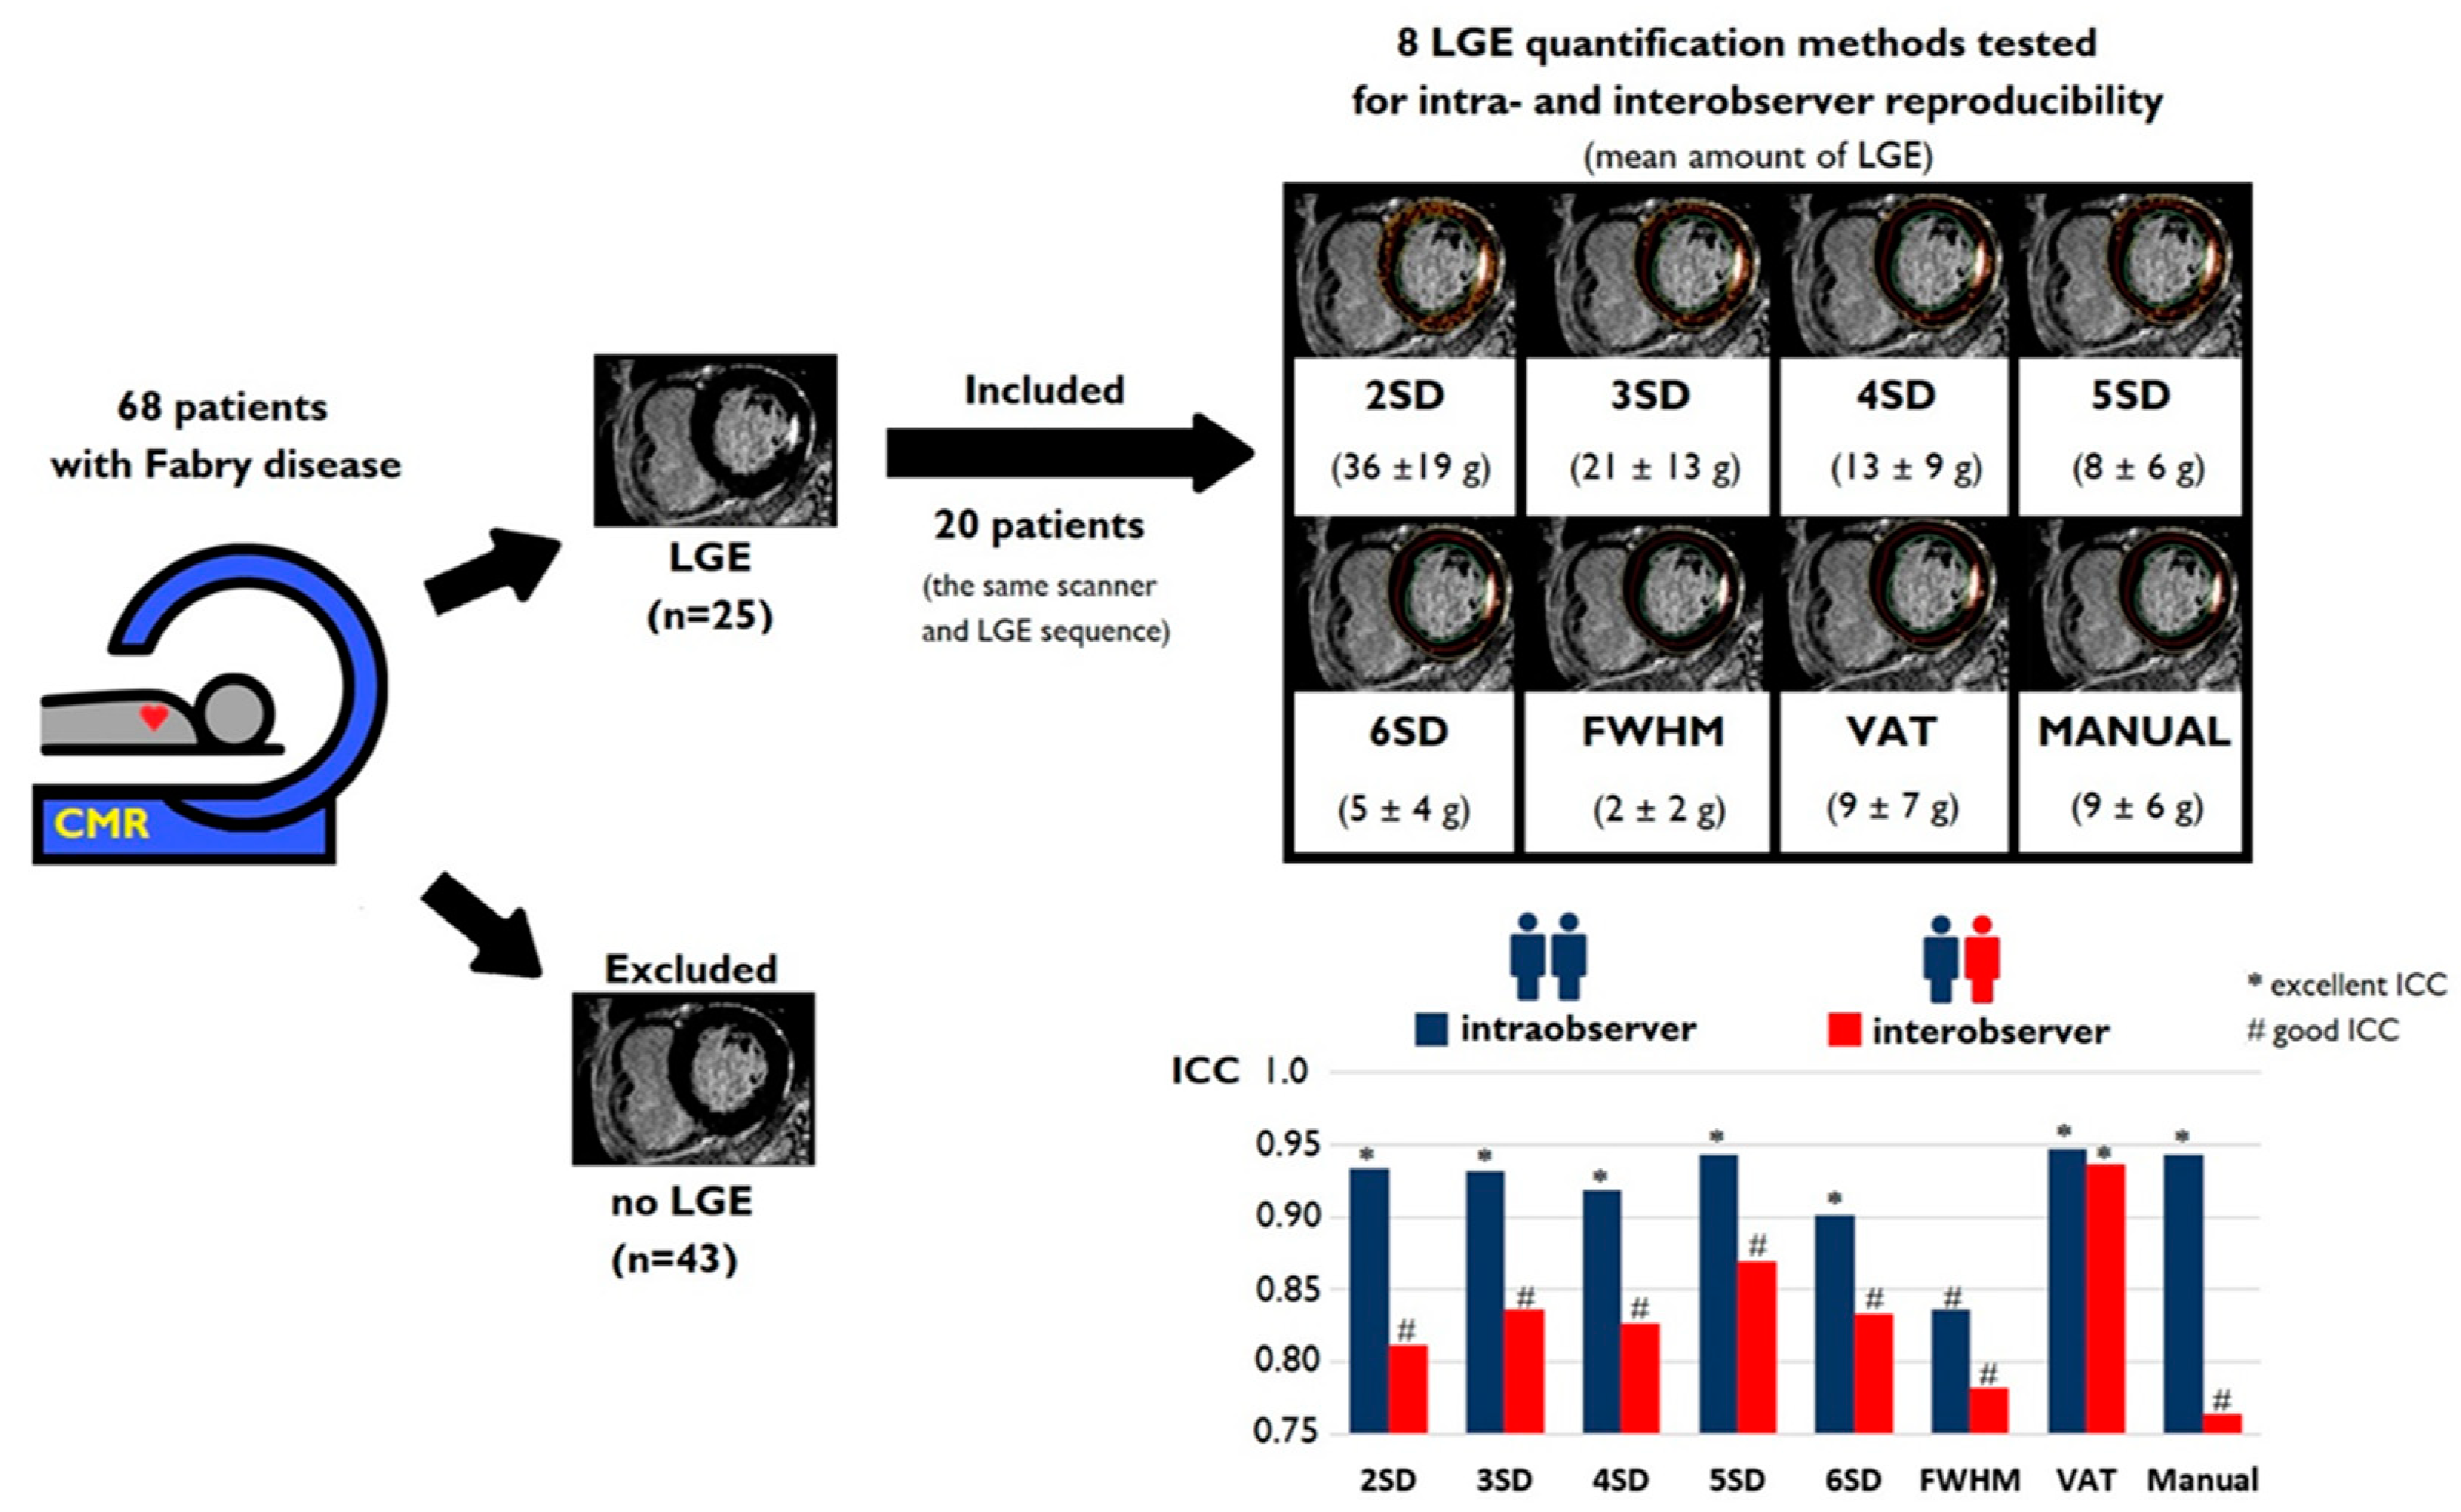

3.2. Amount of LGE

3.3. Intraobserver and Interobserver Reliability and Reproducibility